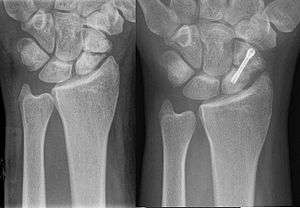

A more obvious scaphoid fracture on a scaphoid view X ray